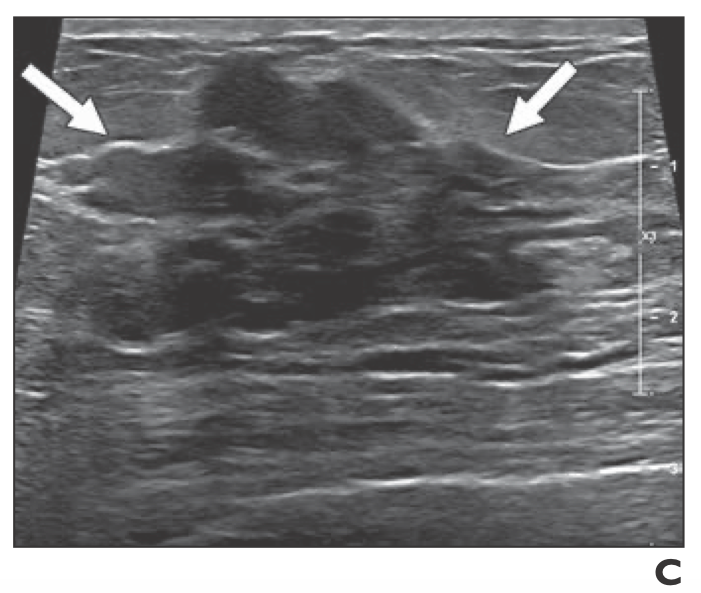

The right breast was normal to palpation Mammography revealed a solid, smooth nodule in the upper internal quadrant of the left breast (Fig 1) Ultrasound demonstrated an oval mass in the 10o'clock position of the left breast measuring 15×10 mm (Fig 2)Breast Cancer ICD10 Code Reference Sheet FEMALE Right C Malignant neoplasm of nipple and areola, right female breast C Malignant neoplasm of central portion, right female breast C Malignant neoplasm of upperinner quadrant, right female breast In the left breast there are two adjacent oval solid lesions measuring 5 and 65mm in diameter present in the 2 o'clock position In the 7 o'clock position there is a larger oval lesion measuring 10 x 5mm The appearance of each of the three lesions within the left breast is consistent, but not diagnostic of fibroadenoma